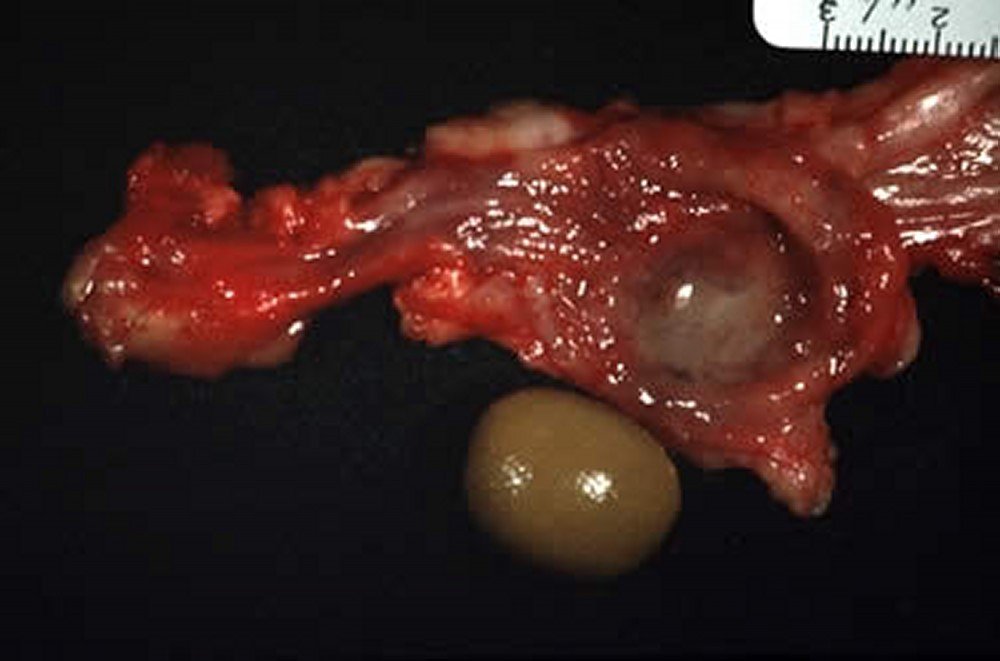

1. سرطان الغدة الرحمية (Uterine Adenocarcinoma)

- أكثر الأورام شيوعًا في الأرانب، خاصة الإناث غير المعقّمة فوق عمر 3 سنوات.

- قد تصل نسبة الإصابة إلى 60% في بعض الدراسات.

- غالبًا ما يتأثر القرنان الرحميان معًا، وتظهر كتل متعددة يمكن تحسّسها.

- ينتشر الورم إلى الكبد والرئتين وأعضاء أخرى، وقد يصاحبه التهاب أو تكيس في الغدد اللبنية.

الأهمية السريرية

- هذا الورم هو السبب الرئيسي للتوصية بتعقيم الإناث غير المخصصة للتربية، بعمر 4–6 أشهر.